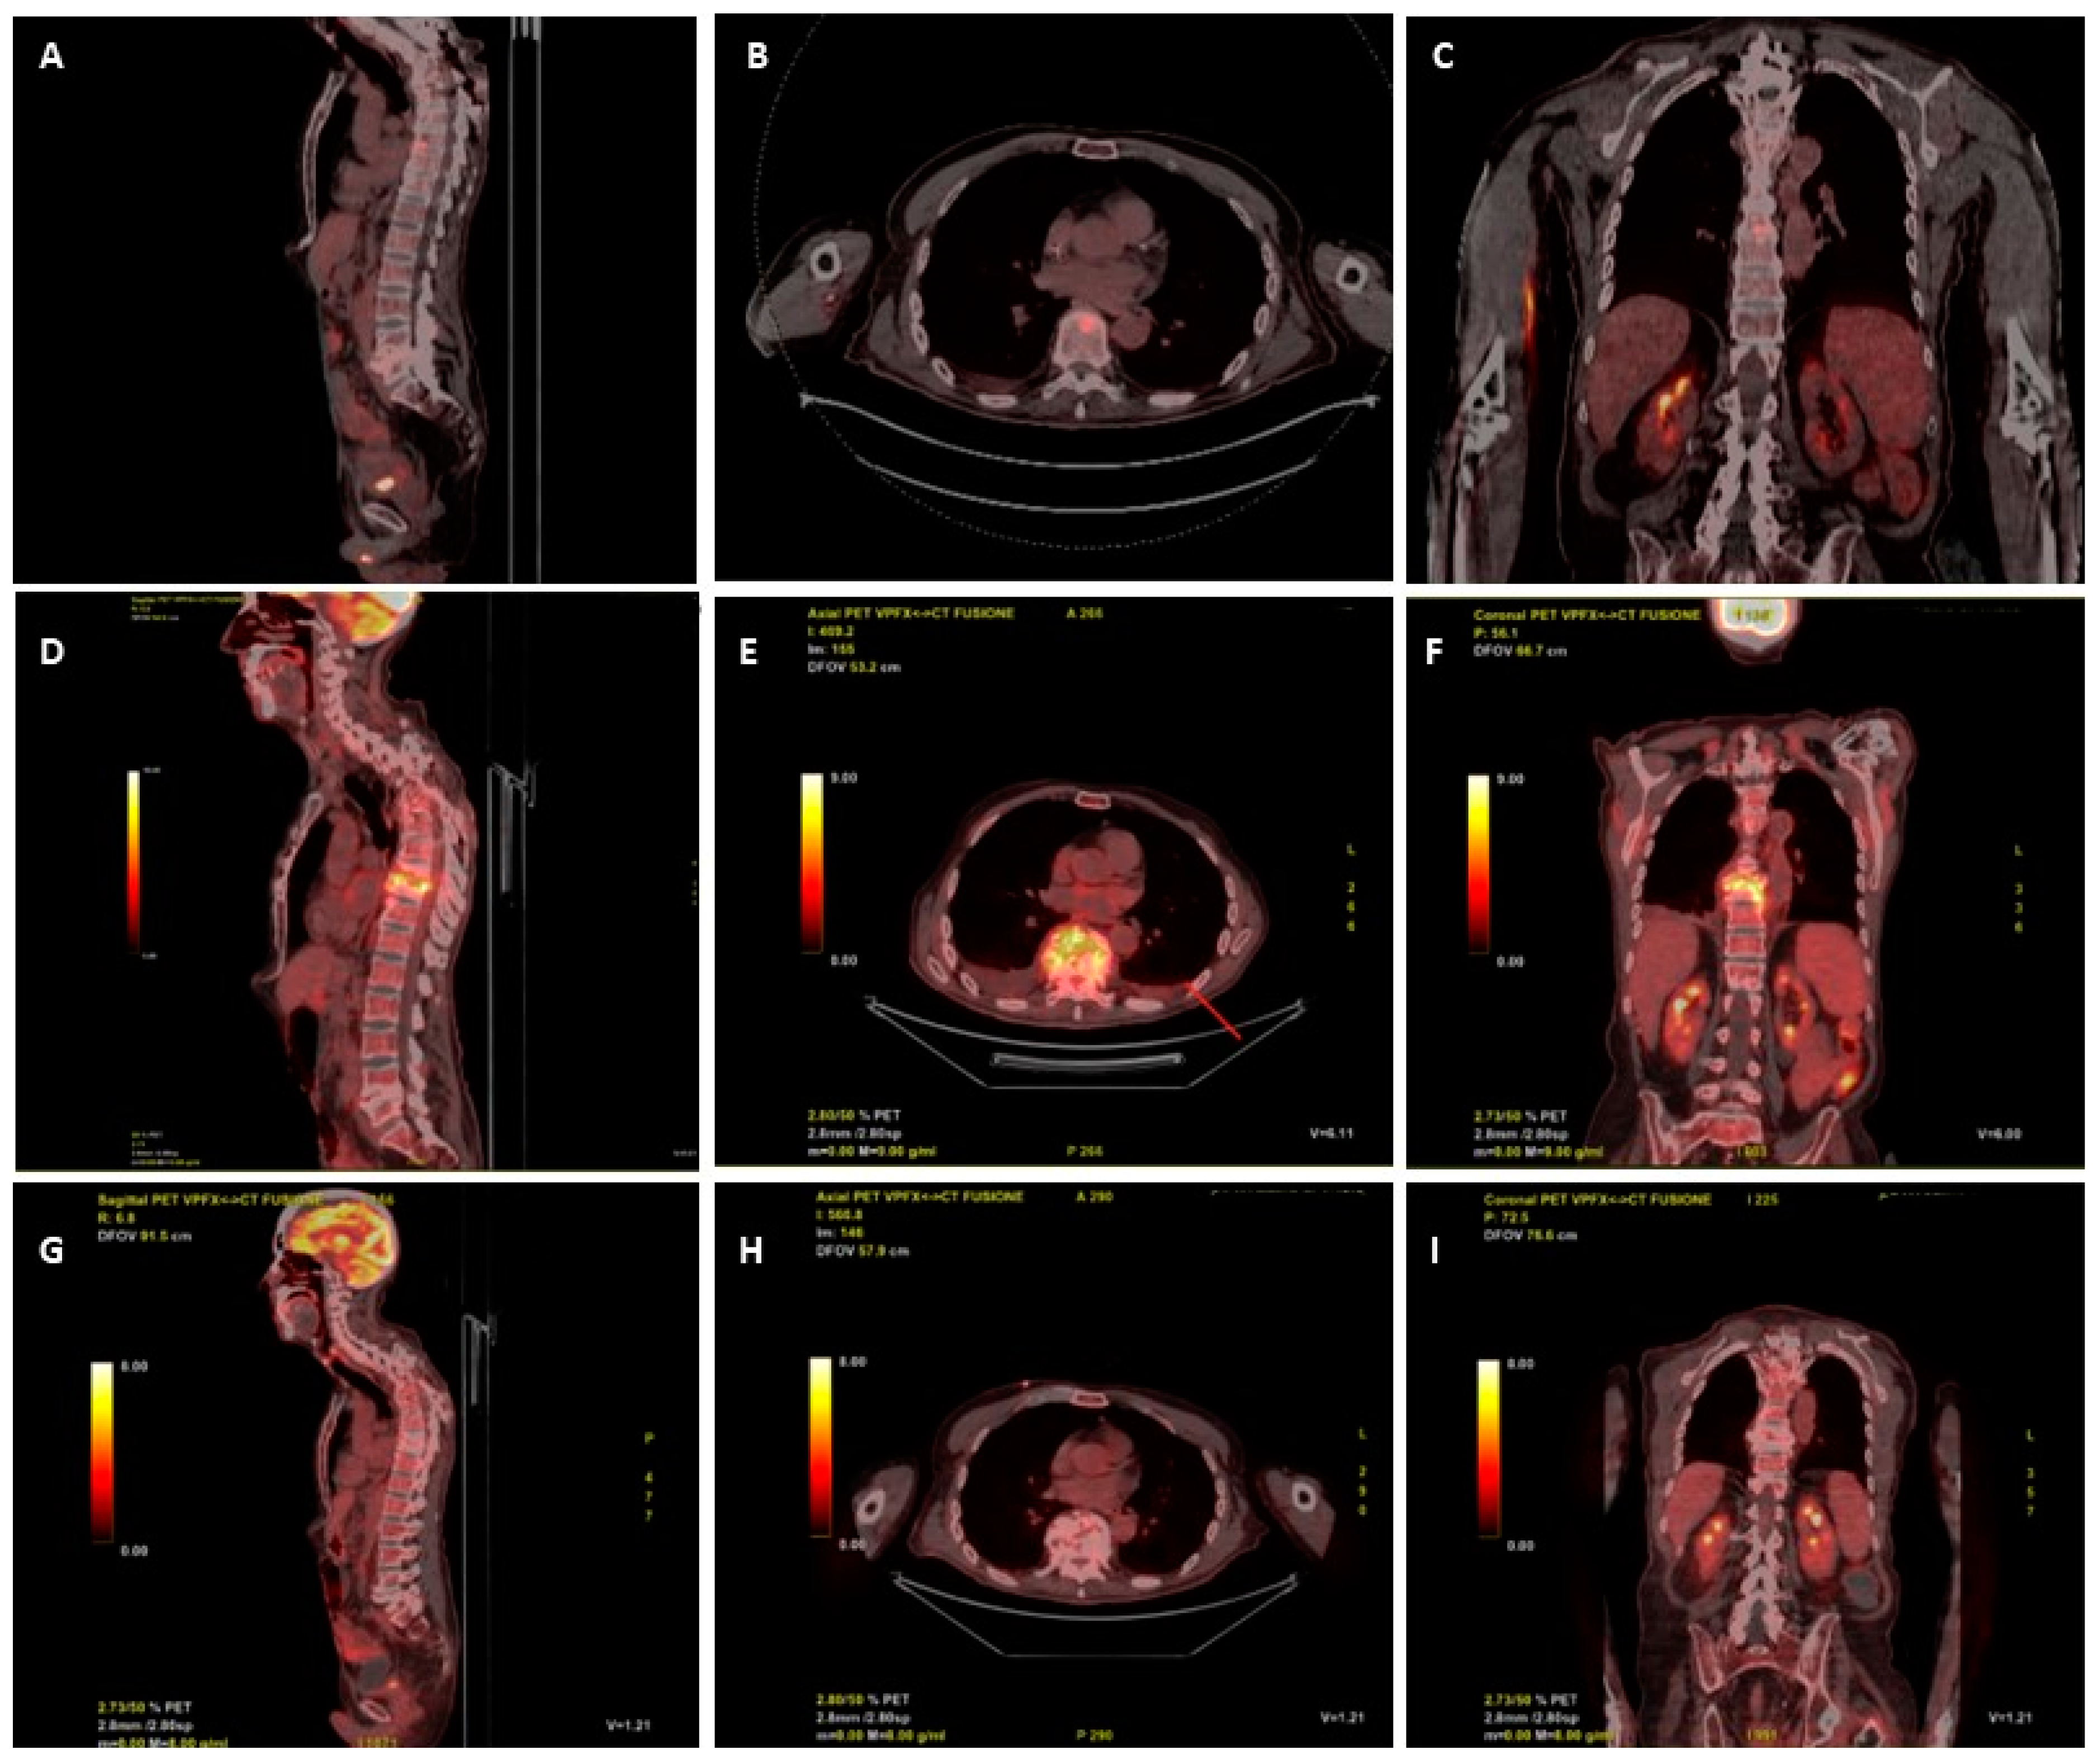

A 18-FDG-PET/CT scan requested on admission for suspected vertebral infection level showed a focal increased uptake in the body of D9 (SUV max 9.5) and in L4-L5 (SUV max 5.9) (Figure 1 A, B, C). Ten days after start of anidulafungin therapy, the patient underwent a trans peduncular bone biopsy of D9, on which culture yielded fluconazole resistant C. parapsilosis, with increased exposure sensitivity to voriconazole and sensitivity to itraconazole and posaconazole (Table 1). The histopathologic examination of biopsy was unremarkable, mostly due to the scarcity of the sample.

He remained in good conditions, with persistently negative serum Beta-D-Glucan (BDG), through all the follow-up, during which he developed, in September and in October, two PICC-related bloodstream infections due to methicillin-resistant Staphylococcus haemolyticus, both treated with dalbavancin 1500 mg i.v. and catheter removal. A new 18-FDG-PET/CT was requested at the end of October, after 11 weeks of rezafungin, that showed increased glucose uptake between D9 and D10 (SUV 15.6), with no uptake at L4-L5 level (Figure 1 D, E, F). A subsequent contrast enhanced spine MRI, performed two days later, showed signs of D8-D9 spondylodiscitis with epidural abscess between D7 and D11. Despite the patient was stable, afebrile and with negative C-reactive protein (CRP) and BDG, in the suspicion of therapeutic failure or coexistence of other diseases (neoplasm, mycobacterial or Staphylococcal superinfection) other multiple vertebral biopsies were collected at D8 and D9, all resulted negative for both mycobacteria (molecular, acid fast stain and culture), fungi, bacteria and with non-specific histopathology. Despite the unexplained radiological worsening, rezafungin was continued.

The patient remained in good condition, with persistently negative serum BDG and CRP, during follow-up. A new 18-FDG-PET/CT performed after 36 weeks of antifungal treatment (and after 26 weeks of rezafungin), showed remarkable reduction of 18-FDG uptake (SUV 2 vs. 15.6) at D9-D10 and no pathologic uptake at L4-L5 (Figure 1 G, H, I), thus, antifungal therapy was stopped.

Figure 1. Digital PET/CT scan reconstruction (Discover GE) after administraton of 250 mCi of 18-FDG: Sagittal (A), axial (B) and coronal planes at diagnosis of spondylodiscitis; Sagittal (D), axial (C) and coronal (F) planes after 11 weeks of rezafungin: Sagittal (G), axial (H) and coronal (I) planes after 26 weeks of rezafungin.